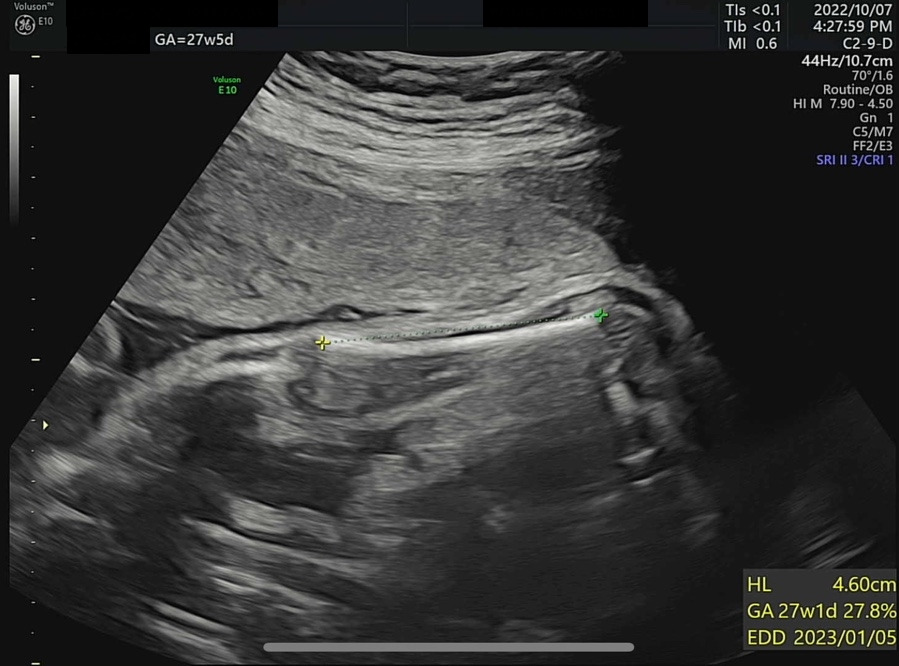

오늘은 병원에서 4D 입체 초음파를 찍기로 예약한 날이다. 입체 초음파는 아기의 모습을 입체적으로 사진 찍듯이 볼 수 있는데, 27주쯤에 찍어야 아기도 통통하게 살이 올라 예쁘게 찍힌다고 하여 이때 예약했다. 초음파실에 들어가서 아기가 주수에 맞게 잘 컸는지부터 확인했다. 2주 전 860g 정도였던 써니는 벌써 1kg를 돌파하여 1096g이 되었다. 임신 28주 이후에 체중이 1000g을 넘은 아기는 조산하여도 NICU(Neonatal Intensive Care Unit, 신생아 집중치료실)에서 치료를 받을 경우 생존 가능성이 95% 이상이다. 가장 친한 친구 중 한 명이 NICU 간호사인데, 매번 써니의 체중을 물어보았었다(직업병..?). 이제 1kg를 넘었으니 혹시나 세상에 일찍 나와도 이모한테 가면 살 수 있다. 그래도 이모 일터에는 가지 말자 써니야...

왼쪽부터 복부 둘레, 허벅지뼈 길이와 예상 체중(머리 좌우직경과 복부 둘레로 예측), 팔뚝뼈 길이